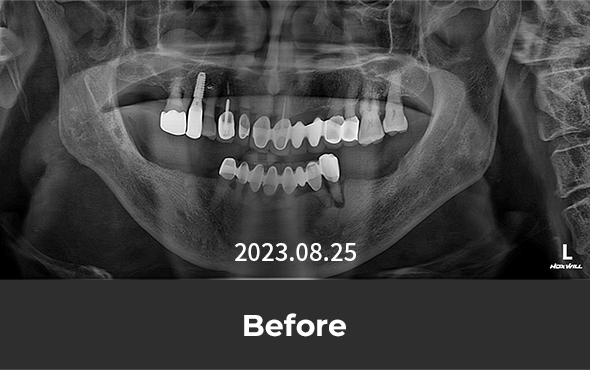

· 네비게이션 임플란트 / 좌측 어금니 식립 case

치료 후 사진은

자세히보기에서 확인하실 수 있습니다.

+ 자세히보기